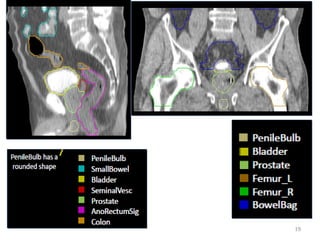

International consensus guidelines on Clinical

Target Volume delineation in rectal cancer

• Consensus was obtained for delineation of the CTV

for elective irradiation of all regional lymph node

levels.

• Seven subsites at risk were identified: presacral

space (PS), mesorectum (M), lateral lymph nodes

(LLN), external iliac nodes (EIN), inguinal nodes (IN),

ischiorectal fossa (IRF) and sphincter complex (SC).

15

Radiotherapy and Oncology 120 (2016) 195–201

http://dx.doi.org/10.1016/j.radonc.2016.07.017